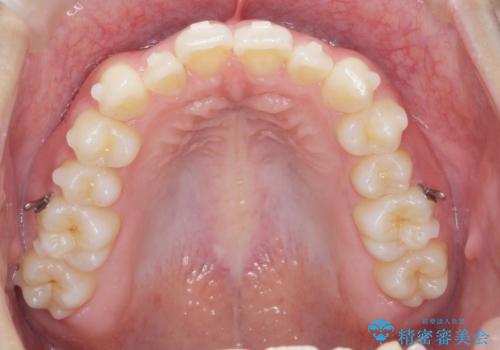

ガタつきの改善 マウスピース矯正治療

- 歯のがたつきの改善を求めて、矯正治療を希望され来院されました。

少量の歯のディスキング、歯列弓拡大、アタッチメントを装着することで審美的な歯列へとマウスピース矯正インビザラインを用いて治療を行います。

マウスピース矯正は装着時間の遵守が非常に大切ですが、しっかりと20時間/日以上の装着を守っていただいたおかげで良好な治療結果を得ることができました。